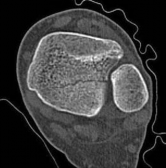

Standard orthogonal radiographs (anteroposterior and lateral) are insufficient for evaluating tibial fractures with suspected plafond extension. A dedicated computed tomography (CT) scan of the ankle with coronal, sagittal, and 3D reconstructions is mandatory.

The CT scan serves several critical functions. First, it identifies the exact location and orientation of the articular split. Second, it dictates the trajectory of the independent articular lag screws, ensuring they are placed perfectly perpendicular to the fracture plane. Third, and perhaps most importantly, it allows the surgeon to map the safe zones for these lag screws so they do not obstruct the planned path of the intramedullary nail.